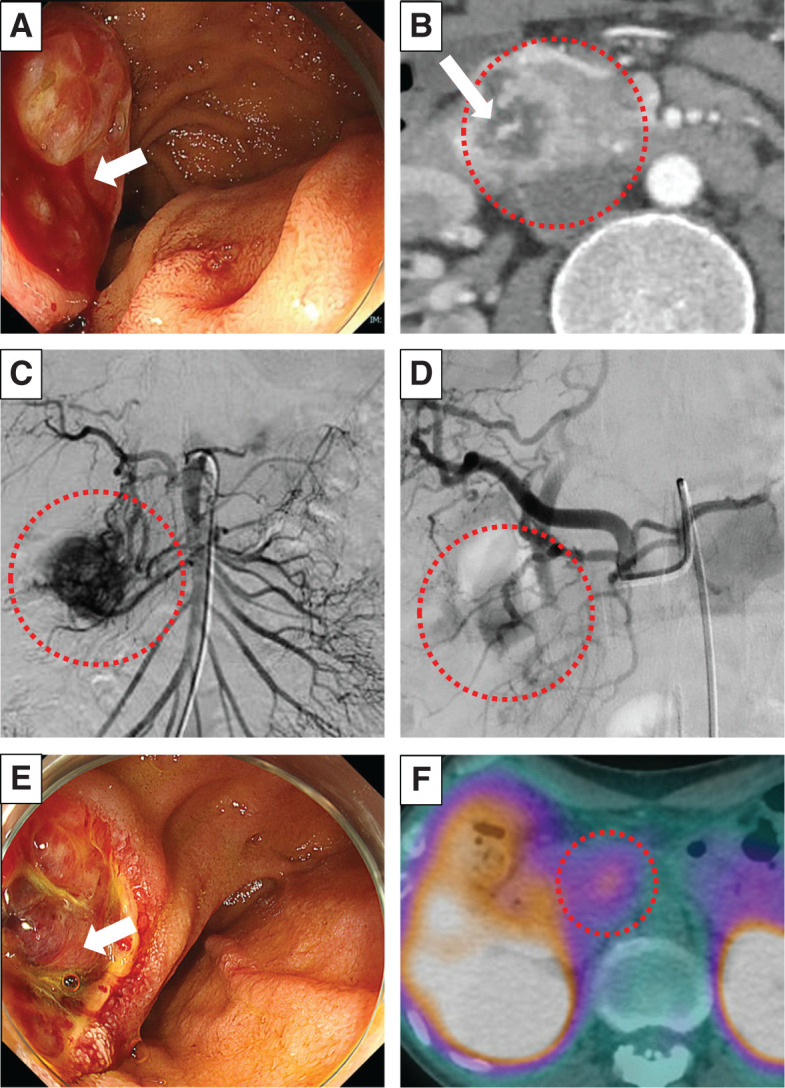

Case presentation: A male patient in his 30s had been diagnosed with VHL disease and had been followed for cerebellar and spinal hemangioblastomas, and renal cell carcinoma, for which he had undergone several tumor resections, radiation therapy, and a ventriculoperitoneal shunt. A pancreatic head tumor deemed to be a neuroendocrine tumor on imaging findings exhibited a gradual increase in size from 12 to 33 mm for the past 2 years, but it had been monitored due to his comorbidities and declining daily living activities. Severe anemia was detected during his regular outpatient visit, and an emergency esophagogastroduodenoscopy revealed a submucosal tumor near the duodenal papilla with ulceration and active bleeding, making endoscopic hemostasis challenging. Dynamic contrast-enhanced CT showed active bleeding from the pancreatic tumor. Subsequently, emergency angiography was performed via the superior mesenteric artery, successfully embolizing vessels supplied by the inferior pancreaticoduodenal artery to achieve hemostasis. Due to concerns about rebleeding, we performed pancreaticoduodenectomy 1 month after the emergency angiography, during which we awaited the improvement of the patient's overall condition. Microscopic findings of the tumor showed multinodular proliferation with hematoxylin-eosin staining, revealing cells with clear cytoplasm and abundant capillaries and dilated branching vessels within the nests. Immunohistochemical analysis demonstrated positivity for alpha-inhibin and S100, with partial positivity for carbonic anhydrase IX, leading to a diagnosis of pancreatic hemangioblastoma.